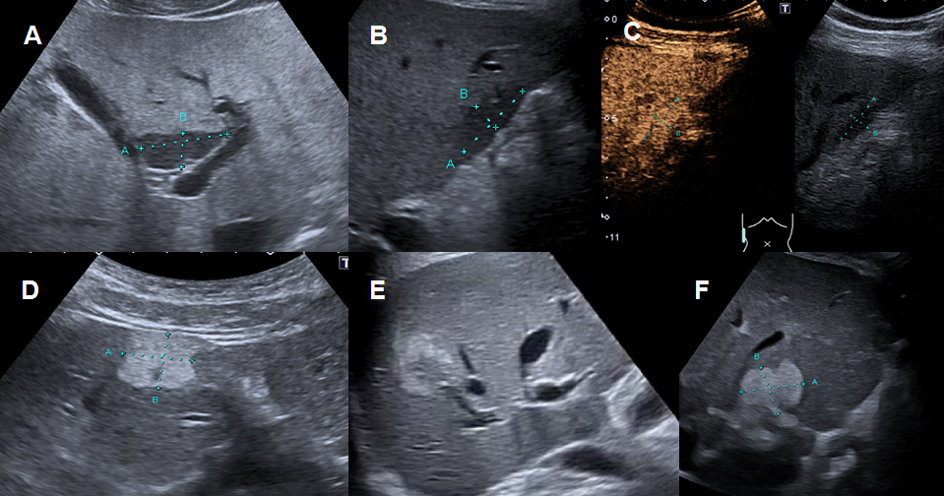

The most common focal liver lesions are either areas with increased (focal steatosis) or decreased steatosis (focal non-steatosis). Focal fatty-sparing areas are typically located in the gallbladder fossa, the periportal region and the segment of the ligamentum falciforme (figure 3A). Similar locations are observed for focal infiltrations of steatosis (figure 3D–F) [22, 23]. These lesions have typically a landscape-shaped appearance but can also mimic solid tumours (so-called pseudotumour). The lesions can be diffuse, focal or multifocal and are often located either in the perivascular or subcapsular regions [24]. Conventional ultrasound imaging with typical landscape-shaped findings in typical above-mentioned localisation without mass effect on vessels can easily diagnose these pseudolesions (hypoechoic in fatty-sparing and hyperechoic in the focal infiltration of fat) [23, 24]. In cases of atypical appearance and localisation (figures 3E, 3F), particularly in patients with risk factors (table 1), CEUS is accurate in most cases [3]. Perfusion of such lesions is isoechoic (figure 3C) in comparison to the surrounding liver tissue and neither hyperenhancement nor washout can be documented on CEUS imaging. In unclear situations contrast-enhanced CT or MRI should be used as next non-invasive imaging modality [22–25].

Figure 3Regional fatty sparing and focal steatosis on ultrasound and CEUS. A Focal sparing periportal in a fatty liver on US. B Focal sparing subcapsular on US C without wash-out (= isoenhancing) in the late venous phase. D Focal steatosis in a female patient. E Focal inhomogeneous steatosis in a young patient with cystic fibrosis. F Focal steatosis in a young female patient.